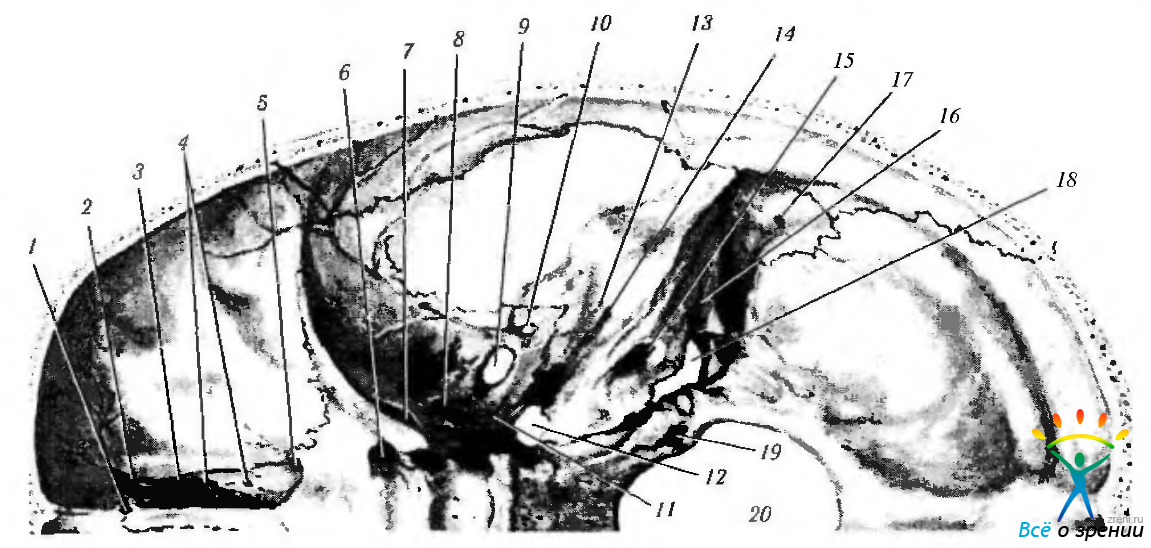

Анатомические изображения срединной сагиттальной линии черепа